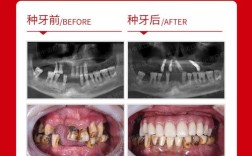

拔牙后立即种牙,又称即刻种植技术,是指在拔除患牙的同期,在新鲜的拔牙窝内直接植入种植体的种植方式,这一技术打破了传统种植需等待拔牙创完全愈合(通常3-6个月)的限制,通过精准的术前评估和精细化的手术操作,实现了“即拔即种”的治疗目标,近年来,随着口腔种植技术的进步和材料学的发展,即刻种植因能显著缩短治疗周期、减少手术次数、最大限度保存牙槽骨等优势,逐渐成为牙列缺损修复的重要选择,但并非所有情况都适用,需严格把控适应症与禁忌症,同时规范操作流程以保障治疗效果。

相较于传统分阶段种植,即刻种植在治疗效率、口腔功能及美学修复上具有显著优势,具体如下:

| 保存牙槽骨 | 拔牙后牙槽骨会发生生理性吸收(前牙区3个月内吸收量可达30%),即刻种植体可即刻承担功能性刺激,维持牙槽骨的体积与形态,避免骨量不足导致的植骨需求。 |

| 即刻恢复功能 | 对于符合条件的患者,可在种植体植入后同期制作临时修复体,实现“当天拔牙、当天种牙、当天用牙”,快速恢复咀嚼与美观功能。 |